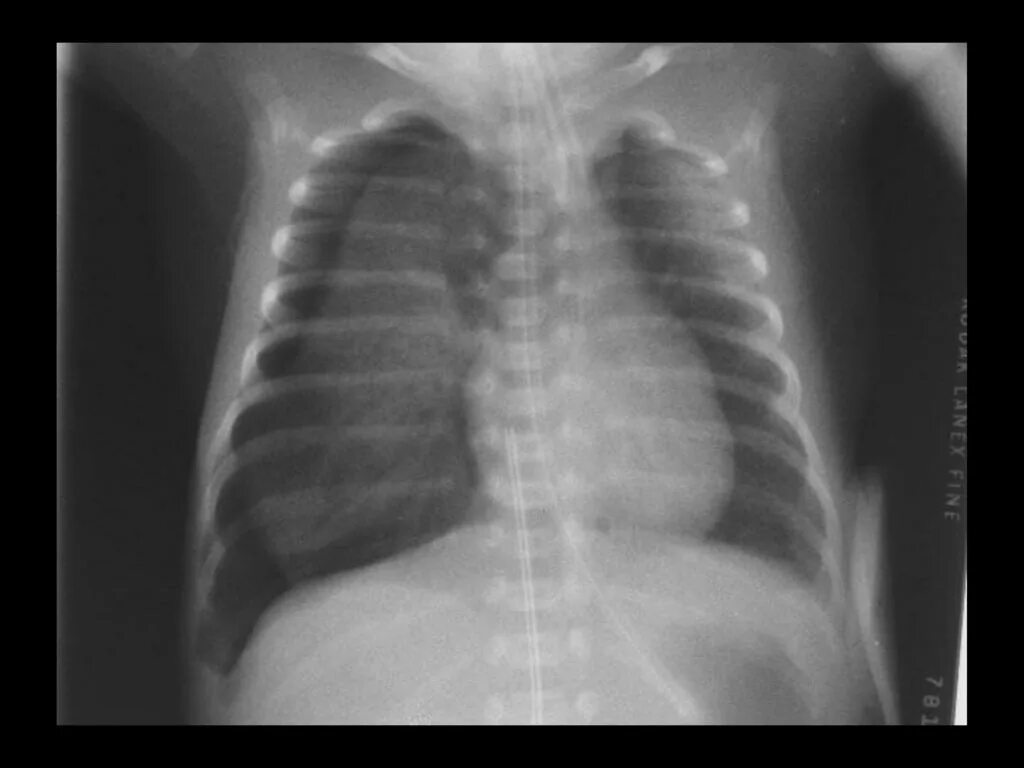

Коллабированное легкое при пневмотораксе